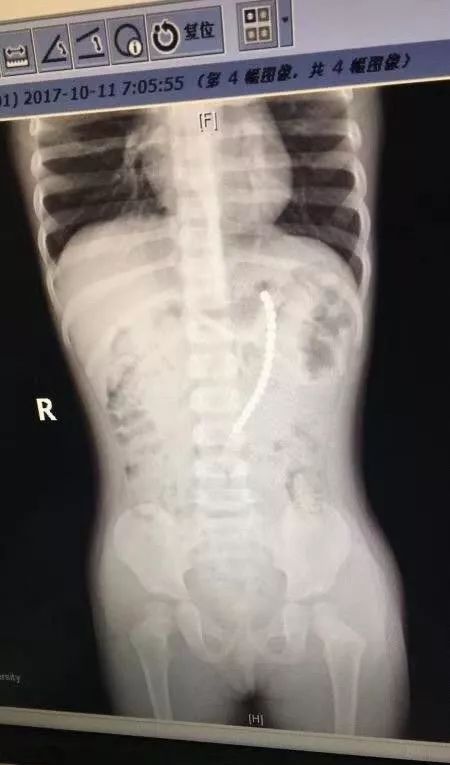

上海市一户二宝家庭 , 父母给7岁的老大购买了一套巴克球 , 两岁的老二一直看着哥哥玩 。 几天前晚上 , 奶奶突然发现二宝正把一颗巴克球往嘴巴里放 , 还说喉咙里不舒服 。 奶奶一听 , 吓坏了!担心孩子把巴克球吞到了肚子里 , 赶快送医 。复旦大学附属儿科医院医生给这个小女娃拍了片子 , 结果 , 人们惊呆了!

一共有19颗珠子在体内!!

---- 玩具还是玩命?又一款危险玩具被列入黑名单! //---- http:// //

复旦大学附属儿科医院副院长、儿外科专家郑珊团队 , 给孩子做了胃镜 , 取出了胃里的六颗巴克球 , 但发现有一排珠子已经穿出胃壁 , 到外面去了 。

在腹腔镜下发现

剩余的珠子一颗连一颗构成一串

一端在胃里 , 另一端在小肠里

也就是说

孩子肠子和胃里面

都被巴克球穿孔了!

医生取出珠子后

再把小女娃的胃和小肠补上

万幸的是 , 这个2岁女孩吞珠后还算送医及时 。 郑珊教授介绍 , 巴克球一旦造成胃壁或是肠壁损伤 , 形成漏洞 , 就意味着大便等可能会漏到腹腔 , 导致腹膜炎甚至引发休克 。